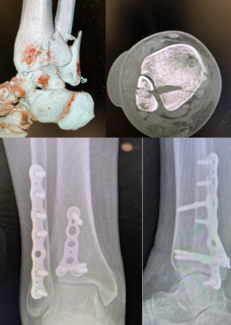

06/01/2024

Ian Barron, DPM, FACFAS

Pantalar dislocations are very rare but can be debilitating and difficult to treat. These authors delve into the background, anatomy, epidemiology, clinical presentation, as well as conservative versus surgical treatment options for pantalar...

Podiatry Today